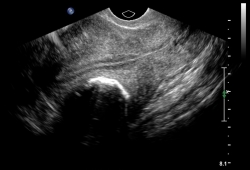

- Polycystic ovary syndrome (PCOS)

- Leiomyomata (uterine fibroids)

- Adenomyosis

- Endometrial polyp